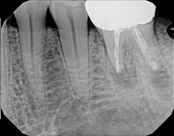

This patient presented with pain when chewing. Diagnostic testing was done and determined it was the lower molar. The diagnosis was: pulpal necrosis, symptomatic periradicular periodontitis. Root canal treatment was performed with laser disinfection. The tooth had a crown and we accessed the tooth through the crown. We saved the tooth and the crown.